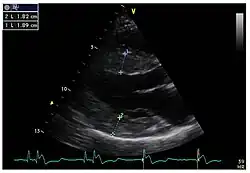

Die linksventrikulären strukturellen Veränderungen des Herzens finden sich bei Morbus-Fabry-Patienten häufig. Mittels Echokardiografie (Ultraschalluntersuchung des Herzens) oder kardialer Magnetresonanztomographie (MRT) können die meist konzentrischen Hypertrophien[80][81] sichtbar gemacht werden. Da mit zunehmendem Alter durch die Ersatzfibrose die linksventrikuläre Hinterwand des Herzens immer dünner wird, ist die Messung der Septumdicke – das ist die Stärke der Scheidewand zwischen linker und rechter Herzhälfte – besonders wichtig. Unabhängig von den strukturellen Veränderungen scheint die Systole, die Phase, in der das Blut aus der linken und rechten Herzkammer herausgepresst wird, bei der Messung mit konventionellen Methoden weitgehend erhalten zu bleiben.[80][81][82][91] Die durch Morbus Fabry verursachte Kardiomyopathie ist durch eine reduzierte Kontraktion und Relaxation des Herzmuskels gekennzeichnet. Gewebedoppler (sowohl tissue velocity imaging als auch strain rate imaging) kann die Herzmuskelfunktion quantifizieren.[7][92] Mit dieser Methode kann die Kardiomyopathie noch vor der Entwicklung einer linksventrikulären Hypertrophie diagnostiziert werden.[91][93]

Parasternale lange Achse: Deutlich sichtbar die linksventrikuläre Hypertrophie mit erhöhter Septumdicke. -

Parasternale kurze Achse: Die Aufnahme zeigt ebenfalls eine linksventrikuläre Hypertrophie. -